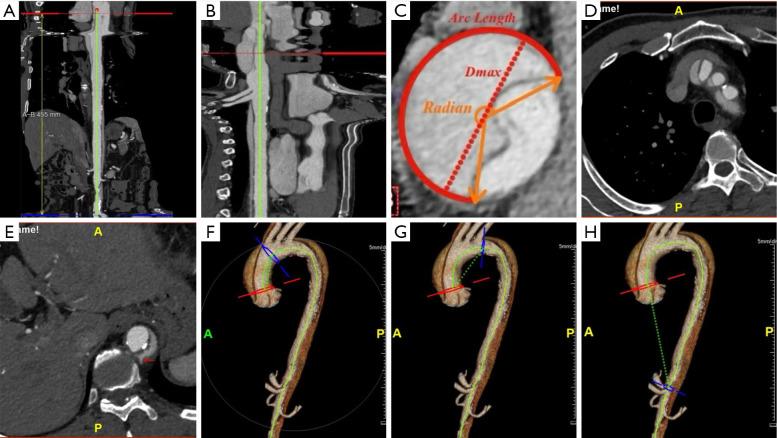

We conducted a retrospective cross-sectional study of TAAD cases treated medically between January 2020 and May 2021 at Xiamen Cardiovascular Hospital. A total of 45 patients were initially enrolled; however, 14 patients who did not undergo computed tomography angiography (CTA) at Xiamen Cardiovascular Hospital and 1 patient whose quality of image was poor were excluded. We analyzed clinical data, including basic characteristics, clinical presentations, and morphological features derived from CTA and reconstructed images for the remaining 30 patients.

Aortic rupture accounted for 82% (14/17) of in-hospital deaths among conservatively treated patients with TAAD. Patients who experienced rupture demonstrated a significantly higher proportion of dissected false lumen (P=0.04), a longer false lumen arc length (P=0.02), and an increased distance from the sinotubular junction to the origin of the celiac trunk (P=0.02). Single factor logistic regression analysis identified two risk factors: arc length ≥130 mm (odds ratio =5.78; 95% confidence interval: 1.12-29.85; P=0.04) and centerline distance from the sinotubular junction to the origin of the celiac trunk ≥391 mm (odds ratio =11; 95% confidence interval: 2-60.57; P=0.006).